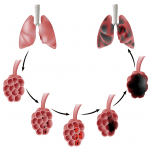

Giãn Phế Nang | Bài giảng CĐHA *

Bệnh khí phế thũng (Pulmonary Emphysema) đặc trưng bởi sự giãn lớn bất thường của các khoảng chứa khí phía xa các tiểu phế quản tận do hủy thành phế nang và mạng lưới các sợi đàn hồi , không có hình ảnh xơ hóa. Nguyên nhân do tổn thương các sợi đàn hồi gây hủy thành phế nang hoặc tắc nghẽn khí lưu thông…